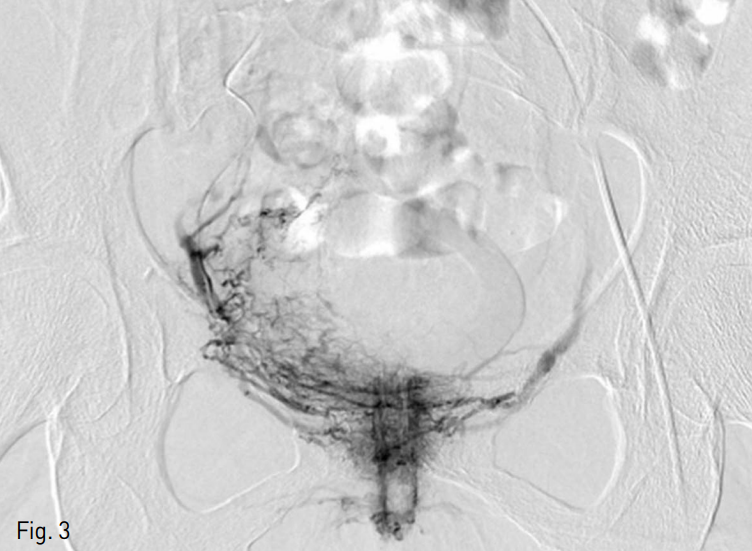

외부 병원에서 시행한 조영 증강 전 복부 CT영상에서 방광 내부에 blood clot 의심되는 소견 있음. 본원에서 시행한 조영 증강 후 복부 CT영상에서 방광벽이 두껍고 조영증강되며 방광주변에 fat strand 관찰되었음 (Fig. 1). 방광내시경에서 blood clot은 관찰되었으나 active bleeding focus는 없었음.

Fig. 1

The post contrast abdominal CT image reveals wall thickening and enhancement of the bladder with perivesical fat strand.